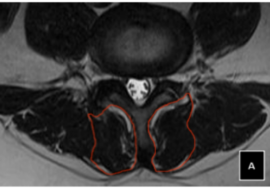

تقوية العضلات الأساسية التي تحيط بالعمود الفقري، خاصة عضلات الجذع والبطن والظهر.

تقوية العضلات الأساسية: العضلات القوية حول العمود الفقري تحميه من الضغط وتحافظ على التوازن.

تعزيز القوة العضلية والتوازن: العضلات المحيطة بالعمود الفقري تصبح أقوى وأكثر قدرة على دعم الجسم.